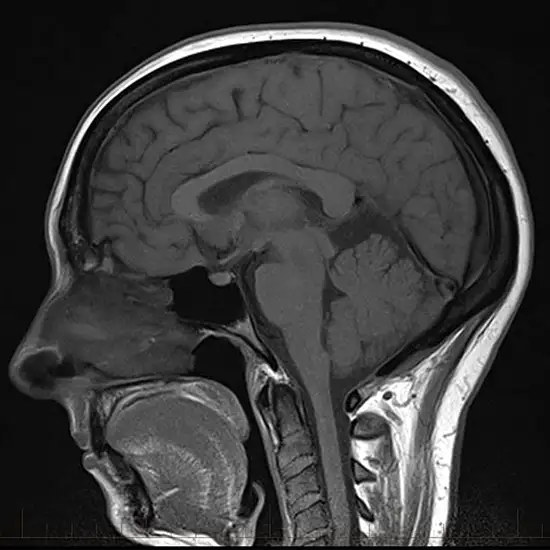

Magnetic resonance imaging (MRI) screening of the brain with the cervical spine and ROI(Region of interest) is an imaging procedure used to evaluate the brain, the neck, and seven cervical spine vertebrae. It helps in identifying a variety of conditions/ problems affecting the brain and upper spine, abnormalities, and problems in the soft tissues within the spinal column. The Region of Interest is the area of the image in the brain or neck that represents a tumour or abnormalities.

The Brain tumour of any kind is fatal because its exact extraction is difficult. Images can be segmented using algorithms of MRI. The non-uniformity in location, shape, and size of the tumour in the brain with the disproportionate distribution of classes in the dataset results in a challenging task. To deal with these challenges, a region of interest (ROI) is extracted from images by removing essential information.